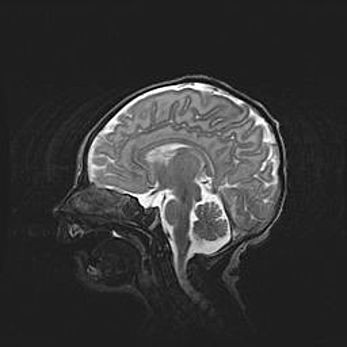

Аномалия Денди-Уокера. Признаки гипоплазии мозолистого тела.

Возраст: 5 месяцев 3 дня

Вес: 5550 г

Пол: мужской

Окружность головы: 39 см

Срок гестации: 40 недель

Аномалия Денди-Уокера – это порок развития головного мозга, для которого характерна триада симптомов: гипотрофия или аплазия червя мозжечка и/или полушарий мозжечка, расширение четвёртого желудочка с формированием ликворной кисты задней черепной ямки, гипертензионная гидроцефалия различной степени.

Гипоплазия мозолистого тела относится к дефектам внутриутробного этапа развития мозговой ткани, возникающим в процессе закладки структур головного мозга, что происходит на начальных этапах развития эмбриона.